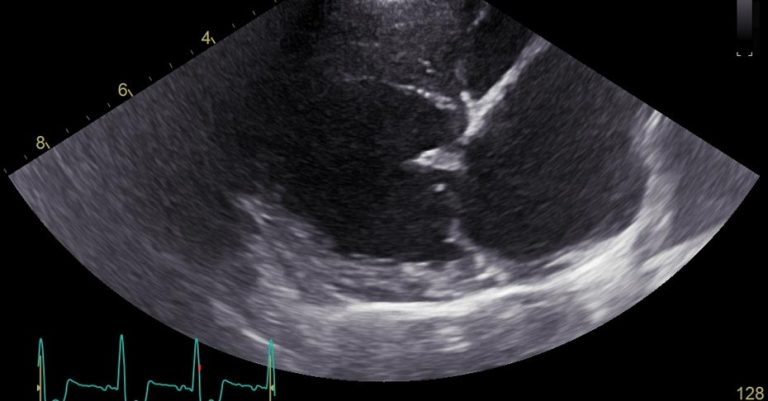

Thoracic radiographs (Figure 2) showed a diffuse, mild interstitial pattern throughout the caudal lung fields, which, combined with the echocardiographic findings (Figure 3; LA:Ao 2.2, LVIDdN 2.44, dilated pulmonary veins, bulging of the interatrial septum into the right and increased left-sided filling pressures, along with a newly detected severe septal leaflet prolapse), suggested early onset left-sided CHF with mild pulmonary oedema.